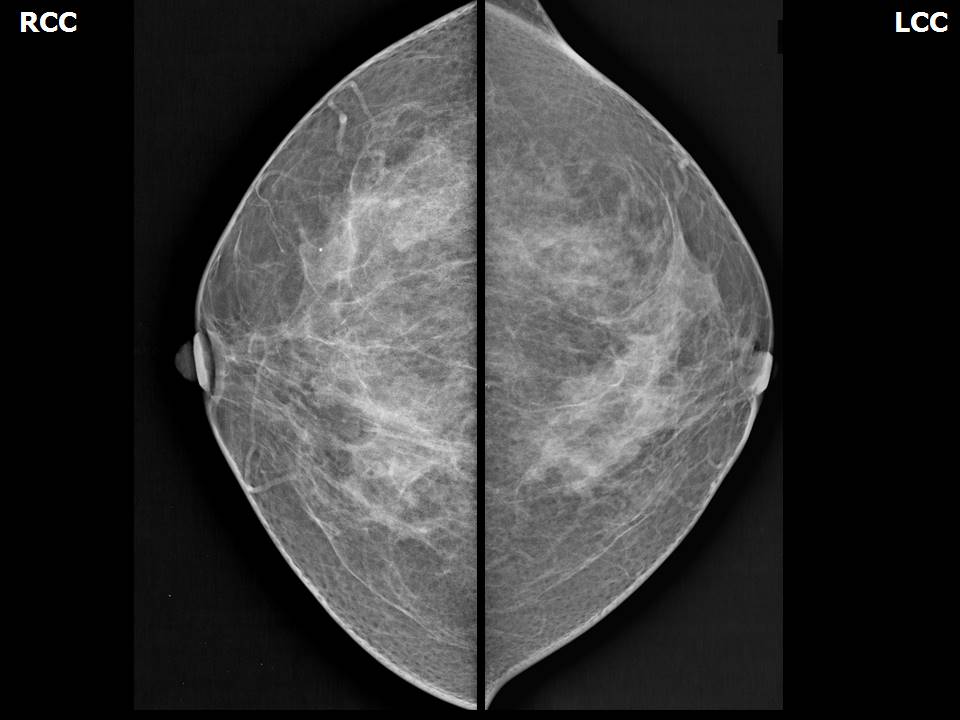

Аномалии молочной железы: медицинские примеры и визуализация